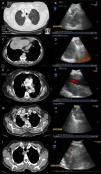

Fig. 1 shows some examples of the computed tomography (CT) and endoscopic ultrasound images obtained.

Examples of radiological and ultrasound images from four of the cases from the series. (A and B) Computed tomography (CT) and endoscopic ultrasound images of a mass located in the right upper lobe, aspirated using endobronchial ultrasound, the result of which was adenocarcinoma of pulmonary origin. (C and D) CT and endoscopic ultrasound images of a patient with a pulmonary lesion in the left lower lobe and lymphadenopathy in right mediastinal station 9. Both were aspirated using endobronchial ultrasound via the oesophagus; the result in both was colon cancer metastasis. (E and F) CT and endoscopic ultrasound images of a left hilar mass surrounding the pulmonary artery, with EBUS-guided needle aspiration diagnostic of adenocarcinoma of pulmonary origin. (G and H) CT and endoscopic ultrasound images of a right paratracheoesophageal mass possibly originating in the right upper lobe, with needle aspiration carried out via the oesophagus, resulting in a diagnosis of adenocarcinoma of pulmonary origin. (I and J) CT and endoscopic ultrasound images of a mass located in the right upper lobe infiltrating the mediastinum. EBUS-guided fine needle aspiration was performed with a result of adenocarcinoma of pulmonary origin.